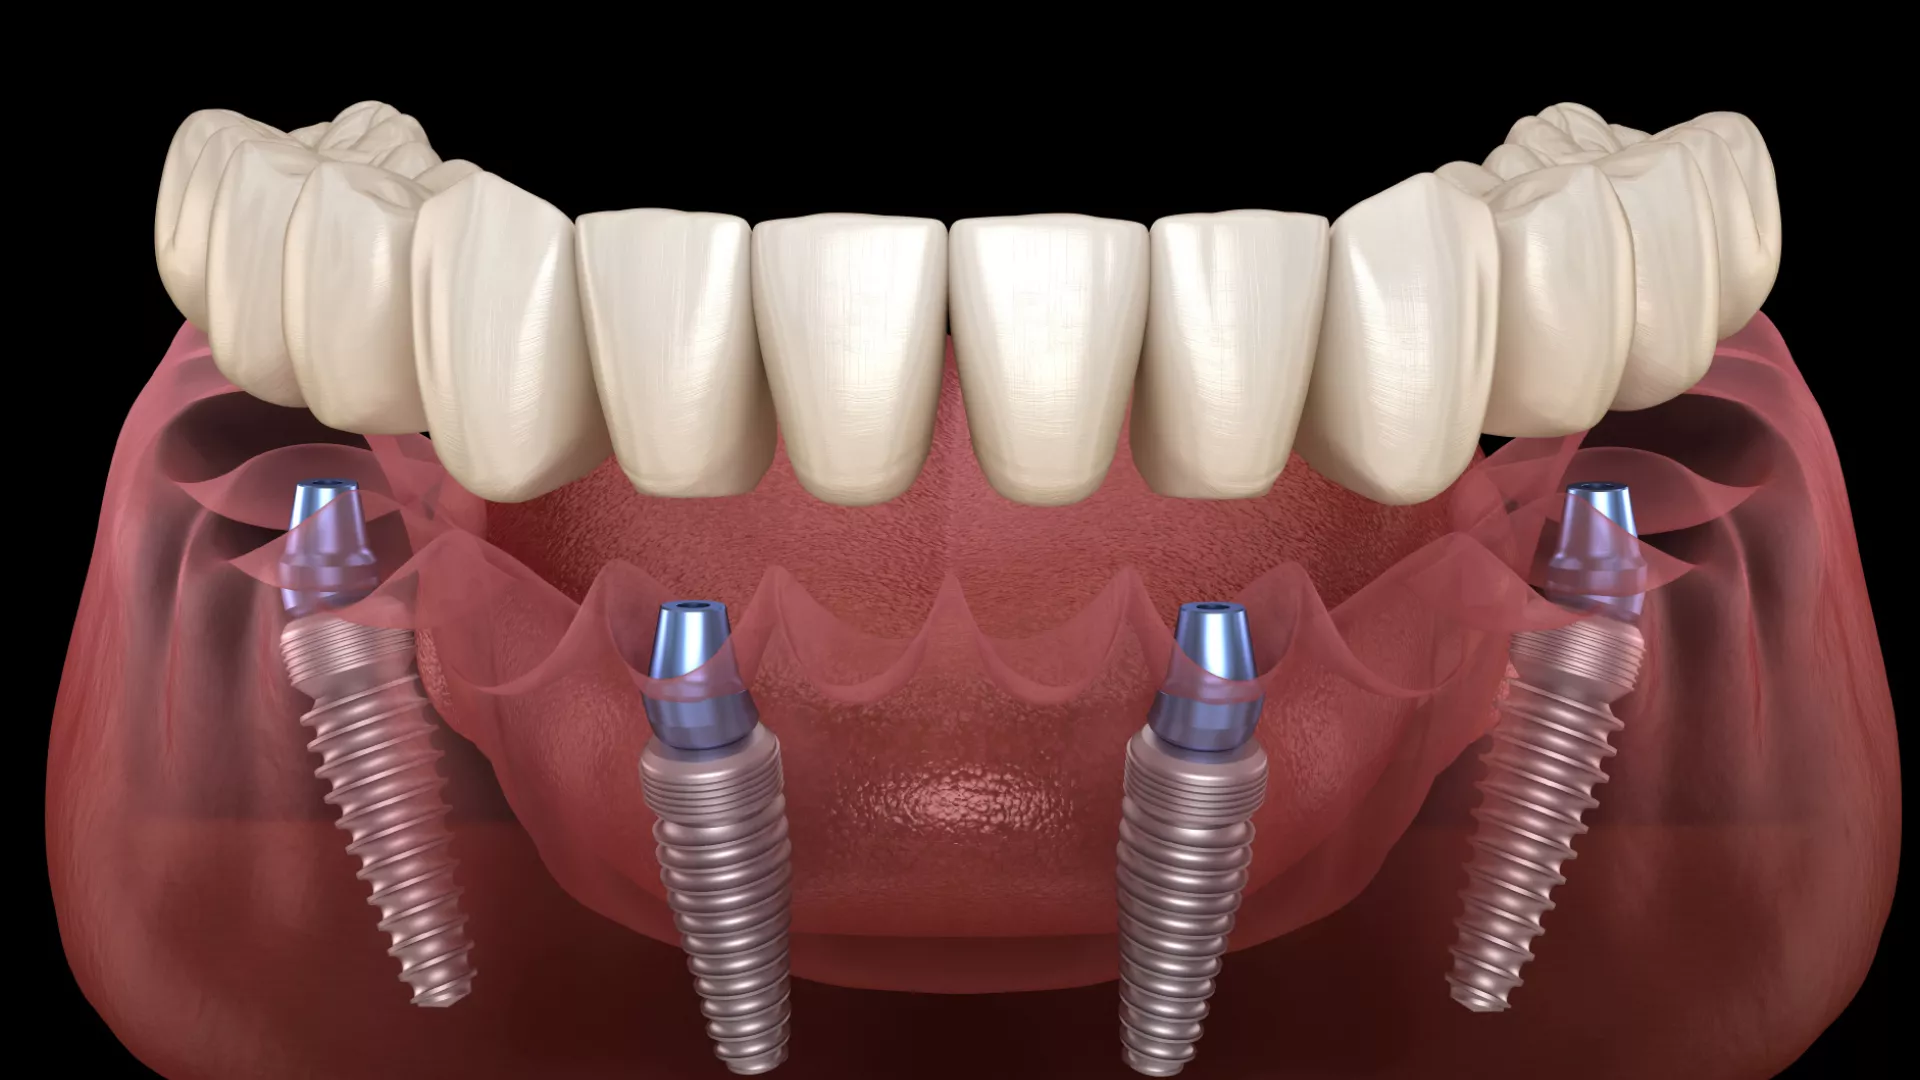

All-on-Four ve All-on-Six İmplant Tedavileri: Modern Dişsizlik Çözümleri

All-on-Four tedavi yöntemi, alt veya üst çenede dişsizlik sorunu yaşayan bireylerin çene kemiğine sadece dört adet implant yerleştirilerek sabit protezlere kavuşmasını sağlayan bir tekniktir. Bu tedavi, Nobel Biocare tarafından geliştirilmiş ve uzun yıllardır başarılı bir şekilde uygulanmaktadır.

Bu yöntemde iki adet implant dik açıyla ön bölgeye, diğer iki implant ise 30-45 derece açıyla arka bölgeye yerleştirilir. Böylece kemiğin en sağlam olduğu alanlardan faydalanılarak daha az sayıda implantla yüksek stabilite sağlanır.

All-on-Six, adından da anlaşılacağı üzere, çene başına altı adet implant kullanılarak tam dişsizlik tedavisine olanak tanıyan bir yöntemdir. Bu uygulama, daha geniş kemik desteği sağlar ve uzun vadeli dayanıklılığı artırabilir.

Altı implantın yerleştirilmesi sayesinde protezin çene kemiğine olan bağlantısı daha dengeli olur. Bu, özellikle kemik yoğunluğu yüksek olan hastalar için ideal bir çözümdür. Diş hekimleri tarafından kemik yapısı yeterli hastalara sıklıkla önerilmektedir.